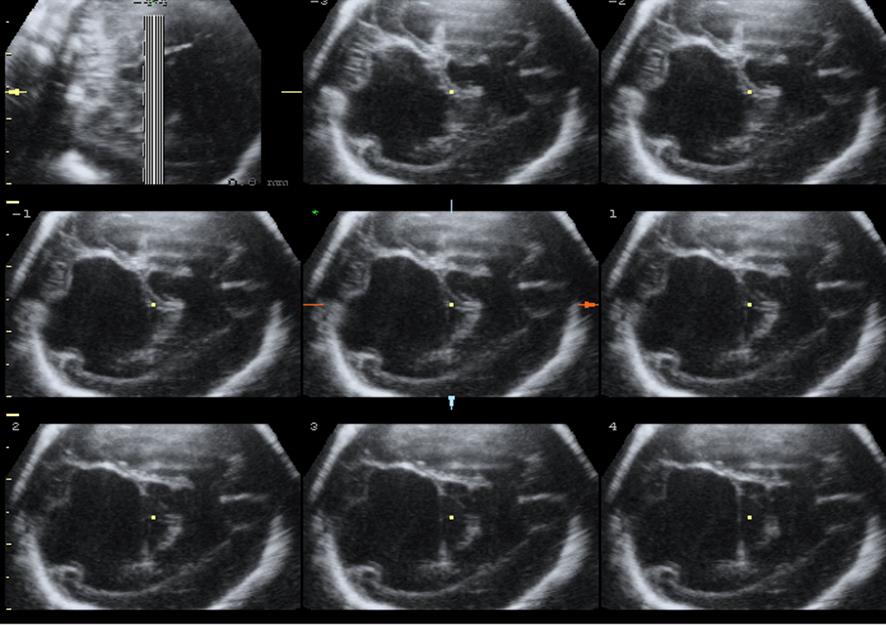

Срок 25 недель. Диагноз?

Ответ на вопрос 6

- Сглаженность контура Сильвиевой борозды, неровный контур желудочков, перивентрикулярная повышенная эхогенность в области переднего рога латерально и герминогенного матрикса.

- Диагноз: мальформация коры головного мозга: лиссэнцефалия, перивентрикулярная гетероротопия.